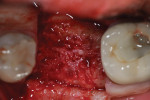

Each socket was treated in one of two manners. If the walls of the socket were determined to be thick and intact, with the diameter not larger than 7 mm to 8 mm, a barrier alone was trimmed to extend 3 mm beyond the socket and placed over the site. If the walls were thinner or if dehiscence or fenestrations were present at the socket, then a bone replacement graft of freeze-dried bone allograft (FDBA) (OraGraft®, LifeNet Health, Inc., www.accesslifenethealth.org) that was hydrated with either sterile water or recombinant platelet-derived growth factor-BB (rh-PDGF-BB) (Osteohealth, www.osteohealth.com) (Figure 2) was placed into the socket and was condensed with light incremental pressure to fill the socket. In two instances a bovine-derived xenograft (BioOss®, Osteohealth) was used mixed with rh-PDGF-BB, as a concurrent internal sinus lift was performed. The polylactic barrier was trimmed to fit the site (Figure 3) so that it also covered the areas where dehiscence or fenestrations were present in the buccal or lingual plate. Flaps were replaced back over the edges of the membrane without purposefully advancing them to achieve primary coverage. The site was sutured with 6-0 expanded polytetrafluoroethylene (ePTFE) (Gore-Tex®, W.L. Gore & Associates, www.gore.com) (Figure 4). For infection control, patients were prescribed amoxicillin 875 mg to be taken twice daily for 7 days, along with topically applying chlorhexidine 0.12% mouthrinse with a cotton swab to the site twice daily for 1 month. If a patient was allergic to amoxicillin, they were prescribed either clindamycin 150 mg four times daily for 7 days, or azithromycin 250 mg with two pills taken on the first day and then one per day for an additional 4 days. Ibuprofen 600 mg or acetominophen with codeine were used for analgesia. Patients were told to refrain from chewing on the site to avoid dislodging the barrier.